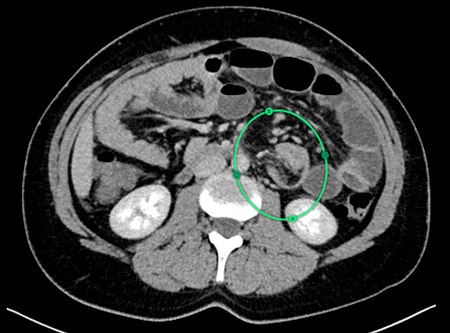

• Tumor Miofibroblástico Inflamatorio. Caso clínico y estado del arte.

Cristian Roa-Cáceres, Miguel Roa-Cáceres

59-63

DOI: https://doi.org/10.11565/arsmed.v50i3.2132